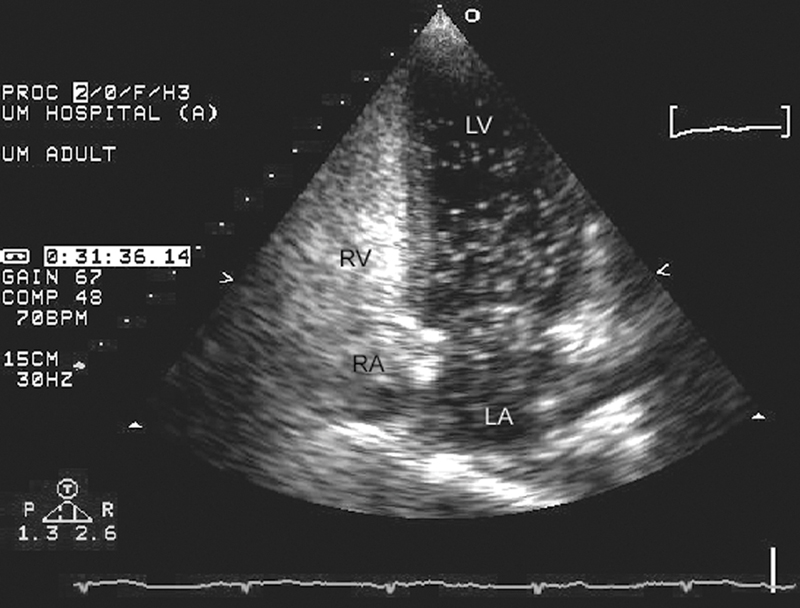

فحوصات تشخيصية لبعض امراض القلب والشرايين التاجية